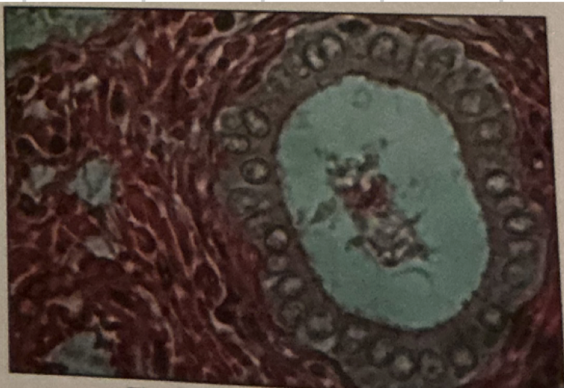

thyroid gland

thyroid gland

contain follicular cells producing thyroxine (T4) and triiodothyronine (T3) from thyroglobulin

parafollicular cells

secrete calcitonin, lower blood calcium; inhibit osteoclast, stimulate osteoblasts

thyroid and parathyroid glands

thyroid gland

bi-lobed structure that lies against & around larynx and trachea

thyrotropin releasing hormone

binds to receptor and produces T4 and T3 from thyroglobulin

parathyroid glands

4 small clusters of tissue; cells that secrete PTH, increase blood calcium, stimulate osteoclast activity